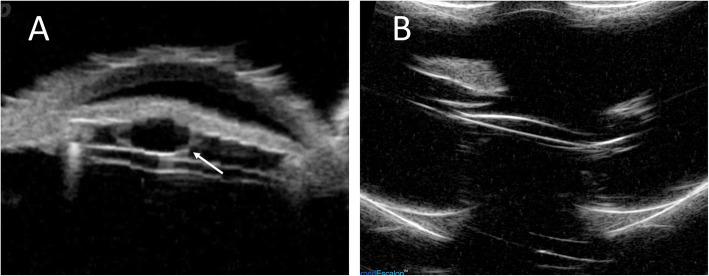

A 64-year-old man who was healthy underwent FLACS for a moderate cataract of his left eye. Shortly after surgery, he achieved 20/20 vision, but anterior bowing of temporal iris was noted on postoperative day 9 with a retro-pupillary iris cyst at temporal-inferior quadrant found after pupil dilatation. The cyst was confirmed by ultrasound bio-microscopy afterward. Four weeks later, argon laser cystotomy was performed, and the cyst disappeared 3 days later. The patient's vision remained stable thereafter.

一位健康的 64 岁男性左眼患有中度白内障,接受了 FLACS。术后不久,他的视力达到了 20/20,但在术后第 9 天发现颞侧虹膜前凸,瞳孔扩张后发现颞下象限有后发性虹膜囊肿。随后通过超声生物显微镜证实了该囊肿。4 周后进行氩激光囊切开术,3 天后囊肿消失。此后,患者的视力保持稳定。